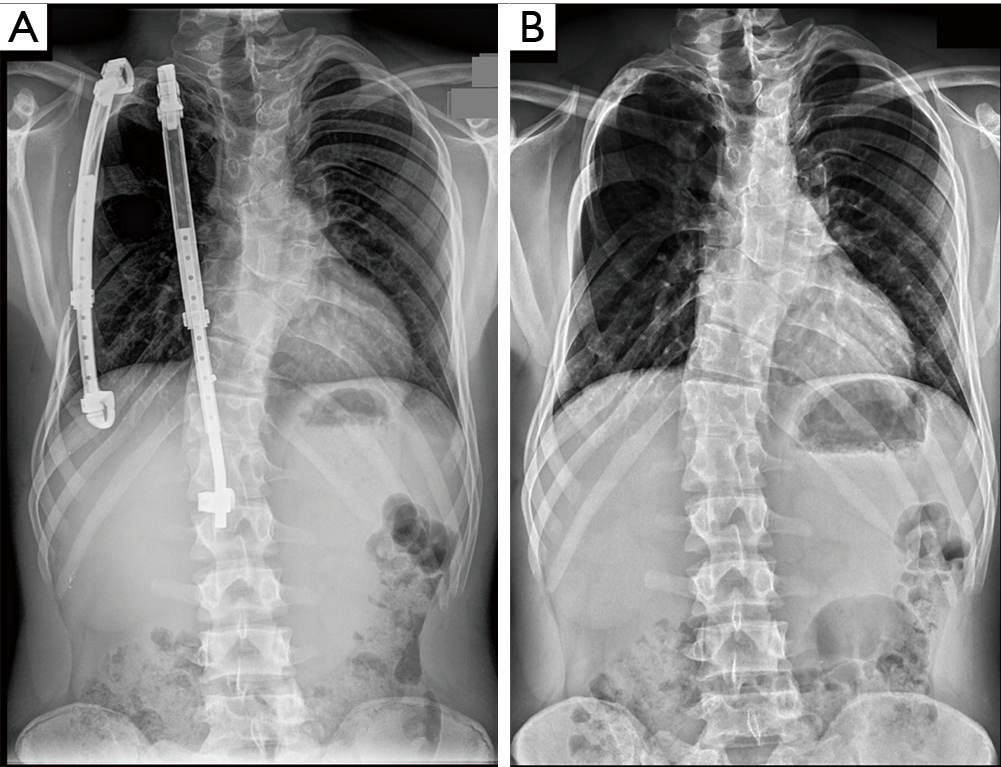

From www.researchgate.net

A, B Scoliosis Xray A AP and B lateral, 1 year post first surgery Titanium Rods For Scoliosis Surgery The harrington rod is a metal rod that is commonly used in scoliosis surgeries performed in the united states. For instrumented correction surgery for adolescent idiopathic scoliosis (ais), surgeons are increasingly. The type of implant used in your surgery will depend on your surgeon's. Most rods are made of titanium, cobalt chromium, or stainless steel. Also known as spinal fusion,. Titanium Rods For Scoliosis Surgery.